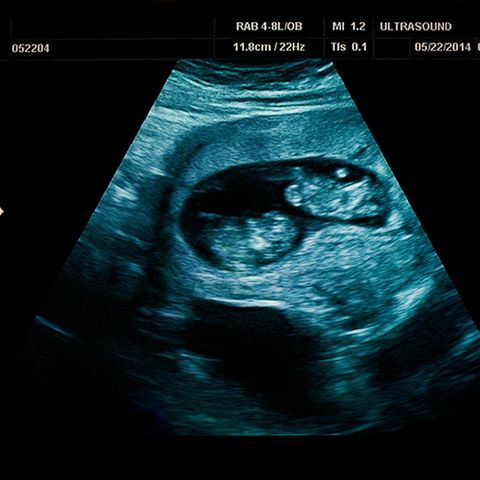

Die 2018 geborenen Geschwister aus dem nordbrasilianischen Bundesstaat Roraima, die bald vier Jahre alt werden, waren sogenannte Craniopagus-Zwillinge. Das bedeutet, dass sie am Kopf verbunden waren, was sehr selten ist. Um sie zu trennen, waren insgesamt neun Operationen nötig, die letzte dauerte 23 Stunden. Das Ärzteteam hatte fast 100 Mitglieder. Erschwert wurde der Eingriff durch die Tatsache, dass die Zwillinge wichtige Gehirngefäße teilten.

Zur Vorbereitung der Eingriffe nutzten die Chirurgen auch virtuelle Realität. Mit Gehirn-Scans erschufen sie eine Art Karte der Köpfe von Arthur und Bernardo und übten die Operationen im Vorfeld. Der an dem Projekt beteiligte britische Chirurg Noor ul Owase Jeelani sprach von "Weltraum"-Technologie. "Es ist einfach wundervoll, es ist großartig, die Anatomie zu sehen und die Operation (virtuell) vorzunehmen, bevor die Kinder irgendeinem Risiko ausgesetzt werden."